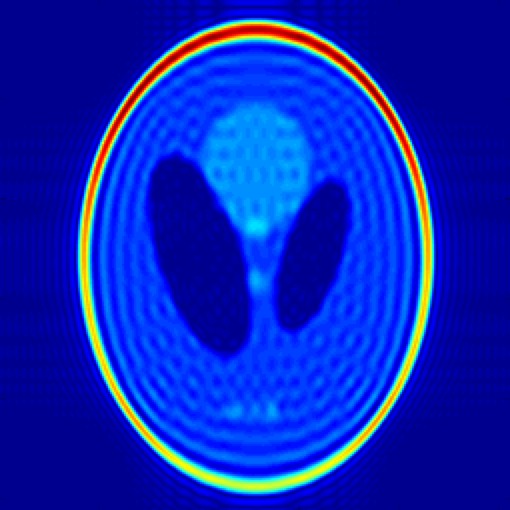

In Fig. 2 we demonstrate the ability of the proposed algorithm to recover a piecewise constant signal from few of its uniform low-resolution Fourier samples. We experiment on simulated data obtained from analytical MRI phantoms derived in [13]. We extrapolate from analytical Fourier samples of the Shepp-Logan phantom to a grid (20-fold undersampling), and recover the signal by performing a inverse DFT. Note that the ringing artifacts observed in the recovery are to be expected due to fact we are recovering exact Fourier coefficients of the signal, and could be removed with mild post-processing.

We propose an extension of the annihilating filter method to a wide class of 2-D piecewise smooth functions whose edges are supported on level set of a band-limited function. This enables us to recover an exact continous domain representation of the edge set from few low-frequency Fourier samples. In the case of piecewise constant signals, we derive conditions of the necessary and sufficient number of Fourier samples to ensure exact recovery of the edge set. Lastly, we prosed one-stage algorithm to recover piecewise constant signals by extrapolating the signal in Fourier domain. We demonstrate that we may accurately recover MRI phantoms from few of their low-resolution Fourier samples.